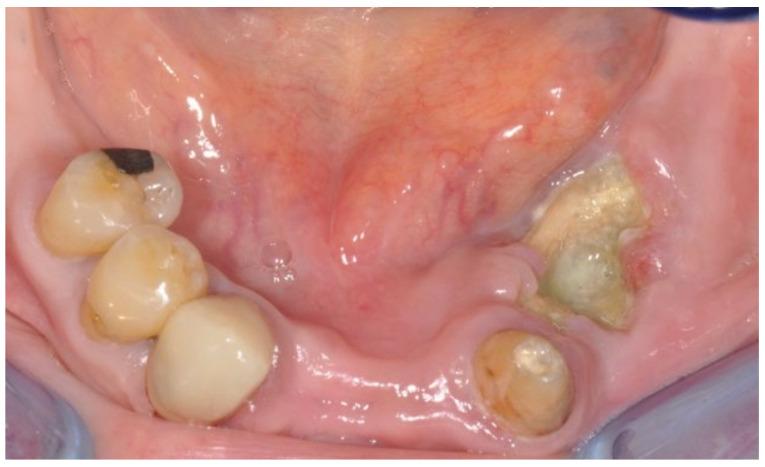

Medication-related osteonecrosis of the jaw (MRONJ) is a drug-related adverse reaction characterized by bone destruction and necrosis in the jaw. This case series aims to evaluate the treatment approaches and outcomes in MRONJ patients.

The retrospective study was conducted at the Dental Unit of the University of Bari, Italy. Patients with MRONJ were treated and followed up for 60 months. The treatment approach involved piezosurgery and concentrated growth factor (CGF). Six clinical cases from this group are described in detail.

None of the patients showed recurrence of necrotic MRONJ lesions during the follow-up period. The surgical interventions, including bone resections and the application of CGF, resulted in successful mucosal healing and the prevention of disease progression.